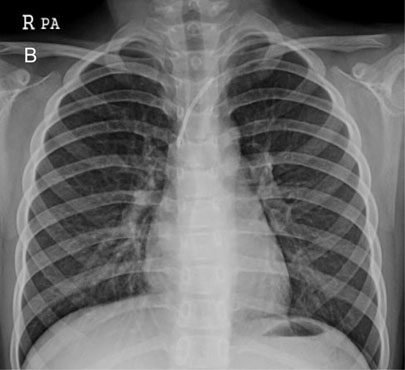

Fig. 1-B

TIVD inserted through Rt. SCV before a removal operation

Fig. 1-B TIVD inserted through Rt. SCV before a removal operation